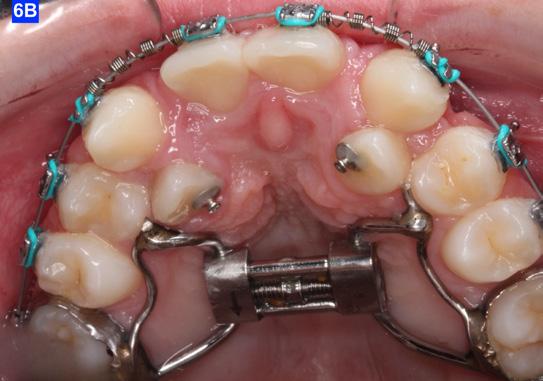

When the maxillary teeth were leveled, we placed a .018 SS arch wire and an OCS to create as much space as possible for the lateral incisors. This technique also allowed us to increase the inclination (torque) of the central incisors as they were too retrusive at the start of the treatment (U1/SN 91°). The maxillary lateral incisors were now completely retracted (Figure 6-A, B).

placed between the maxillary central incisors and the cuspids, on a .018 ss arch wire.8 The purpose of this center bend is to move the roots apart. A side effect of this center bend is that the crowns have a tendency to move together. Therefore, an OCS was placed between the maxillary central incisors and the cuspids. (Figure 10 – A, B)

After the maxillary cuspids were in contact with the second bicuspids, we had to ascertain that there was adequate width in the inter-radicular space. A center bend - “V” pointing gingivally was

To protract the maxillary lateral incisors into the arch, the bite was opened using composite build-ups on the mandibular first molars. The protraction was started with a .012 ligature tie, and the resiliency of the arch wire created the labial movement of the lateral incisors (Figure 10 - C).

Figure 8A: TADs in situ, frontal view 8B: TAD in situ, right lateral view 8C: TAD in situ, left lateral view 8D: Power arms Figure 9A: Maxilla, occlusal view 9B: Maxilla, occlusal view 9C: Maxilla, occlusal view Figure 9D: After the removal of the Hyrax, occlusal view Figure 10A: Center bend “V” pointing gingivally Figure 10B: OCS between the cuspids and the central incisors Figure 10C: Composite build-ups on the mandibular first molars Figure 10D: Adrian “U” bend spring